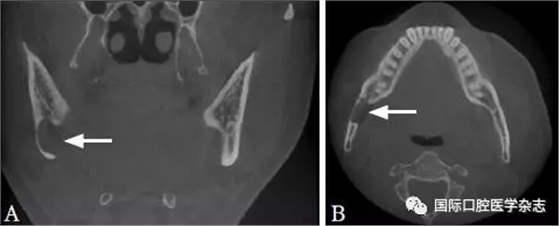

典型病例6 患者的CBCT圖像顯示上下頜骨多發(fā)性的低密度透射區(qū),但牙根完整,未見明顯吸收,牙齒仍有活力(圖6)。

A:矢狀位;B:水平位。

圖 6 骨結(jié)構(gòu)不良的CBCT圖像

Fig 6 CBCT of osseous dysplasia